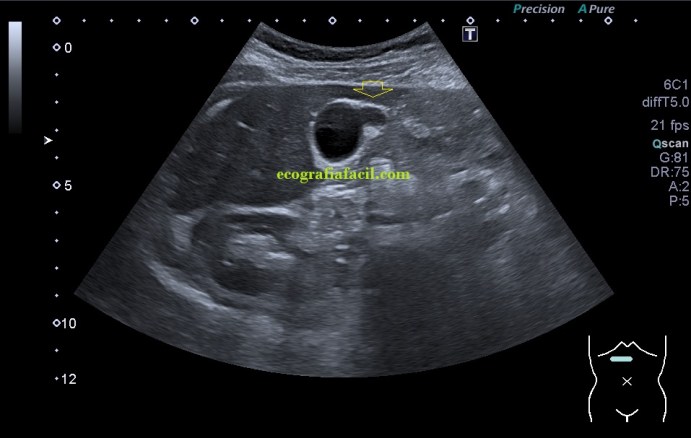

En la imagen 1 la ecoestructura era absolutamente normal, sacular, alargada y anecoica en longitudinal, pero en la imagen 2 se presenta una estructura en una forma anómala, variante de la normalidad, que en ecografía se denomina «vesícula en gorro frigio», su aspecto recuerda a este tipo de gorros de forma cónica con punta curvada que históricamente han acompañado a la humanidad en multitud de situaciones, te dejo el enlace (cultura general) por si te apetece leer un poco…es curioso.

Sumado a esta peculiar presentación encontramos que en la curvatura sacular, en el fundus de la vesícula, «en la punta» que se objetiva en la imagen 2, percibí como si la pared en ese punto estuviera ligeramente engrosada, pero no terminaba de verlo como yo quería así que cambié la sonda, de cónvex a lineal, adapté los parámetros o ajustes ecográficos y la imagen de la pantalla era preciosa, se veía la imagen sacular, muy definida, gracias a la alta frecuencia de la sonda lineal, con una definición muy importante que me permitió documentar como en la pared de la vesícula, imagen 4, existía engrosamiento mural. Se usa el cónvex virtual o trapezoidal, como ajuste que permite ampliar el scan range de la pantalla con el uso de la sonda lineal.